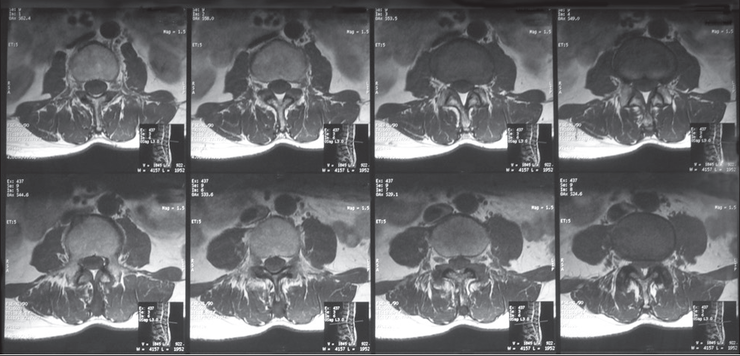

□ MRI : 척추 뼈와 주변 인대, 디스크의 퇴행성 변화로 인해 척추관이 좁아진 것을 확인할 수 있습니다.